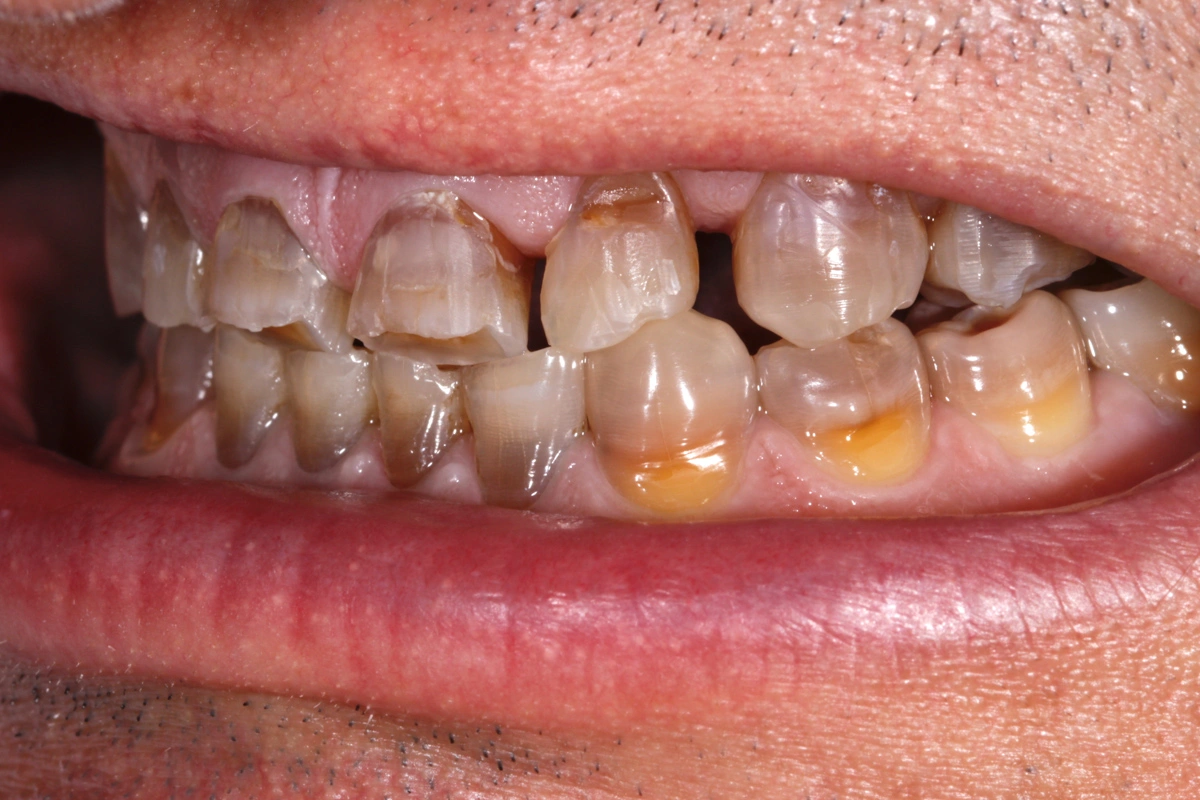

«Rehabilitación completa adhesiva en paciente joven con desgaste dental severo y tinción por tetraciclinas.»

Paciente joven acude a consulta referido por el ortodoncista para tratamiento de desgaste.

La tetraciclina era un medicamento que se administraba en los años 50 que a posteriori se han podido observar los efectos secundarios que tienen en la boca: tinción dental intrínseca. Existen distintos grados y en función de su severidad. Las tinciones por tetraciclinas suponen un reto a nivel restaurador.

En este caso se trata de un paciente con desgaste dental severo y tinción por tetraciclinas grado IV.